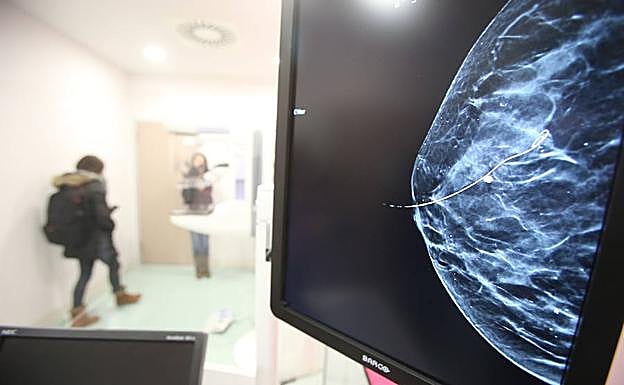

Imagen de una mMamografía.

El primer estudio, descrito como la prueba de cáncer de mama más inclusiva hasta la fecha, encontró que la mayoría de las mujeres con un tipo común de cáncer de mama podría evitar la quimioterapia después de la cirugía, dependiendo de su puntaje en una prueba genética.